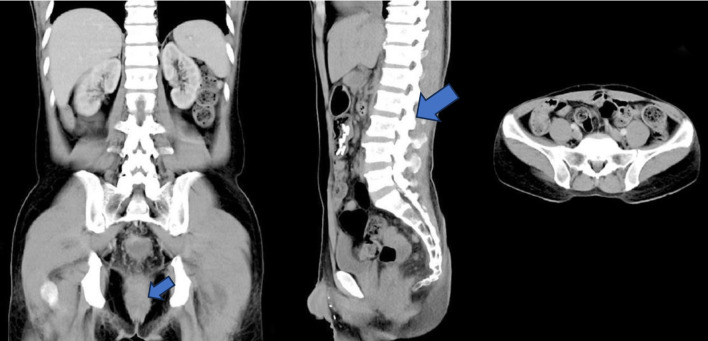

CT检查结果提示为潜在可切除的Ⅳa期CRC:腹部及盆腔CT成像显示直肠区域软组织肿块,自第二骶椎水平延伸至尾骨,疑似侵犯邻近直肠系膜组织(图2)。根据AJCC第八版标准进行临床分期,确定为T3N2bM1a,提示为潜在可切除的Ⅳa期CRC。

图2. 多层螺旋CT图像显示直肠肿块,自S2椎体水平延伸至尾骨,浸润黏膜下层、黏膜肌层和固有肌层,侵犯结直肠周围脂肪组织,伴脂肪条索样改变。膀胱周围、结肠周围、肠系膜、腹主动脉旁及双侧腹股沟区见多发肿大淋巴结。胸膜下可见肺结节,提示肺转移。依据AJCC第八版(2017)分期:T3N2bM1a(ⅣA期)